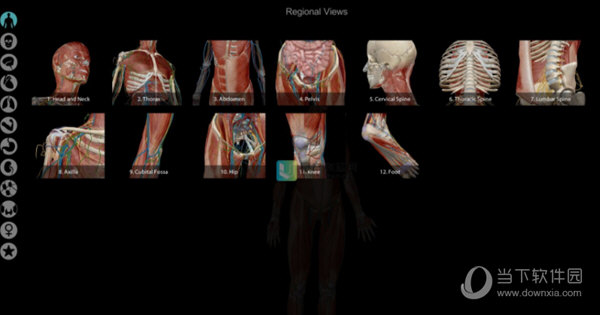

7、点击主界面的左上角VIEWS,可以进入各模块的查看,详细的分支让你更加了解人体构成。